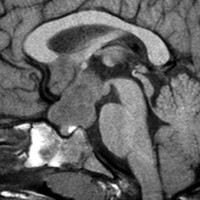

幼児の視路の毛様粘液性星細胞腫です。T2強調画像(左側)で白く高信号に写るのが特徴です。ガドリニウム増強ではまだらになっていますが,均一に真っ白に高信号になることも多いです。乳幼児のものは,ドロドロに柔らかい腫瘍です。

乳幼児時期には,病理組織像が毛様粘液性星細胞腫で,MRI T2で均一な高信号になりガドリニウムで強く増強されます。腫瘍の増大速度は速く,稀には髄液播種することもありそれが腫瘍死の原因となることもあります。奏効率の高い化学療法を早く開始する必要があります。

化学療法が有効なのは,上の画像のようにガドリニウム増強で強く増強されるタイプです,またT2強調画像で強い高信号になるものほど化学療法が有効です,要するに毛様粘液性星細胞腫の要素に化学療法が有効であるということです